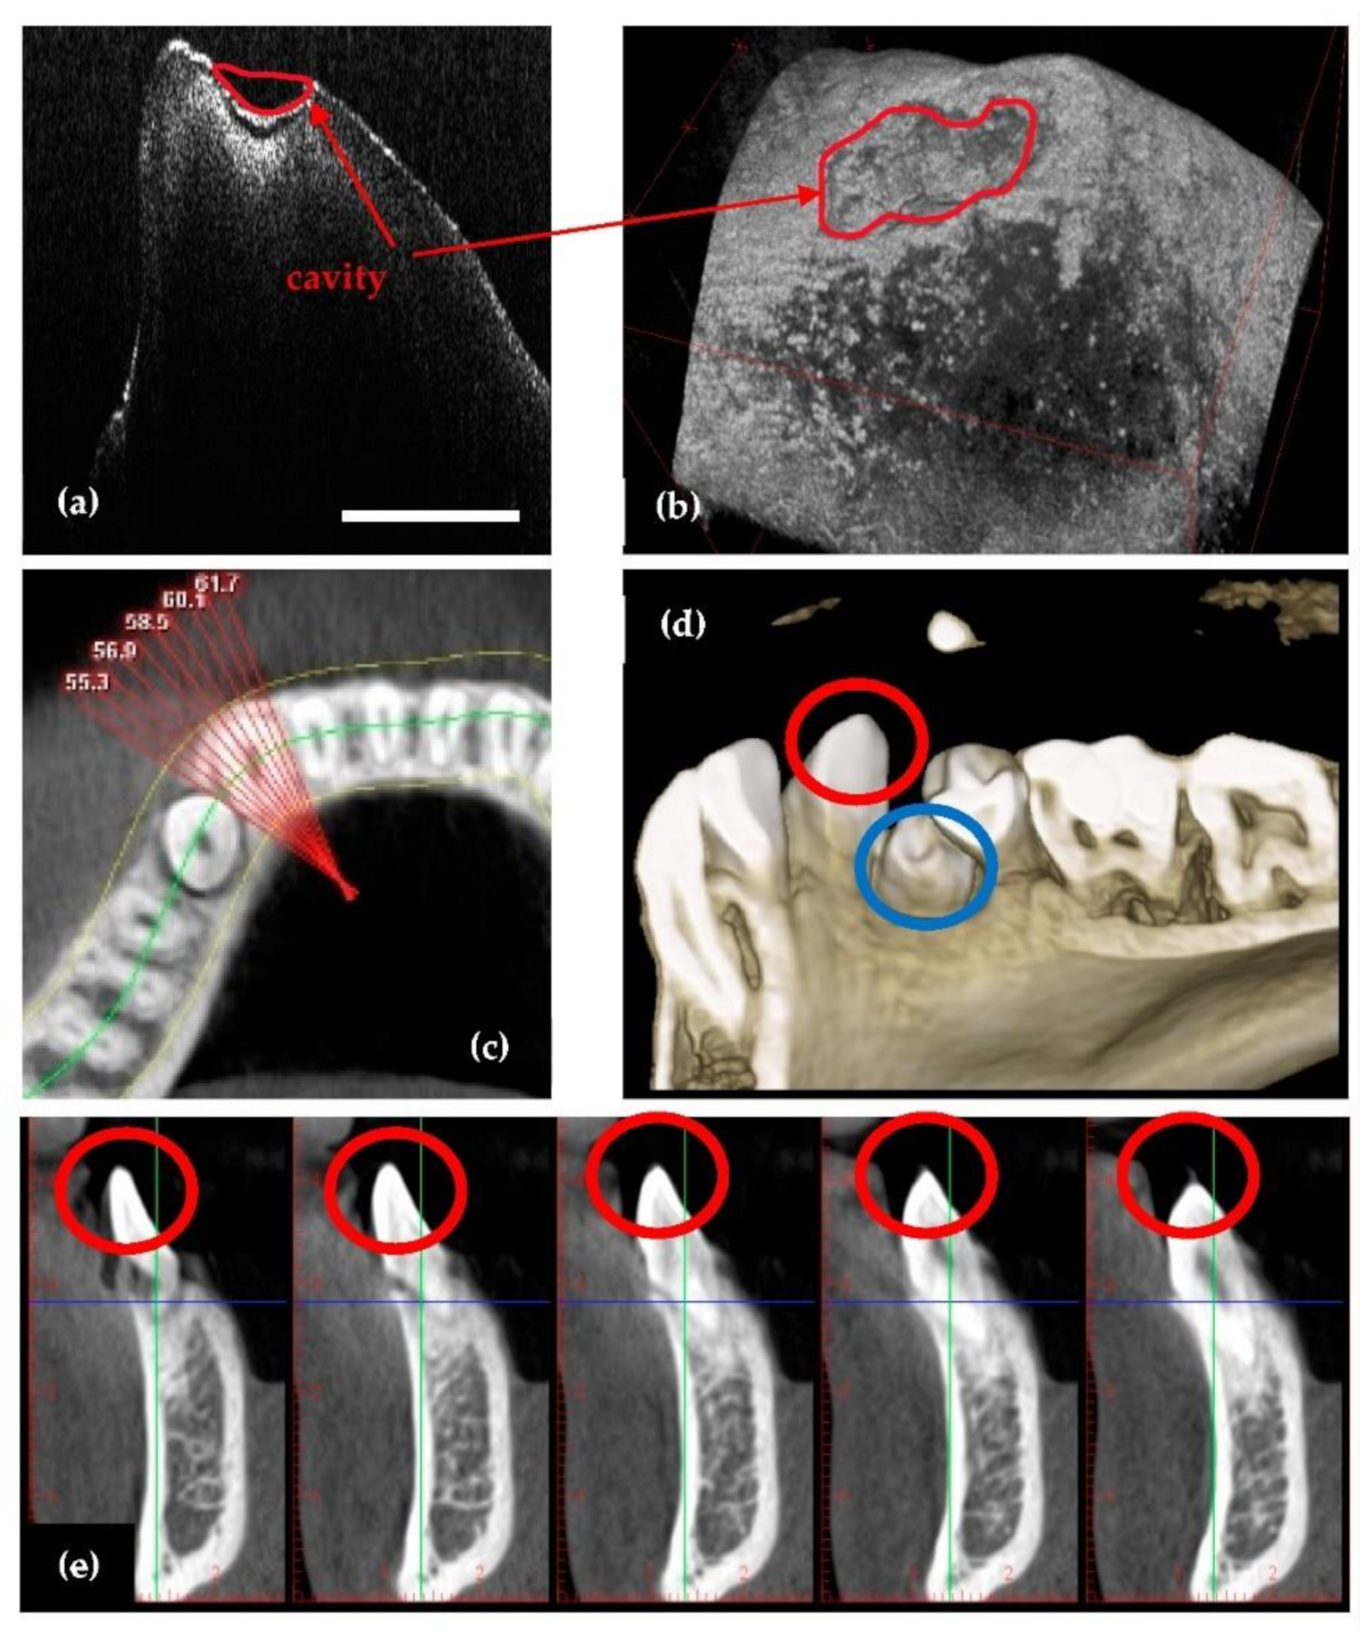

- Because it is using IR laser radiation, OCT does not penetrate metals, although studies of their roughness can be made [46] and, as shown in Figure 4, OCT can provide images near dental crowns, while 3D CBCT for example cannot achieve such images. Also, we have demonstrated that OCT can replace the gold standard of SEM in the study of metallic fractures [47,48]. Therefore, a subject of future work in our groups refers to OCT studies of metallic parts included in the oral cavity, for example dental implants.